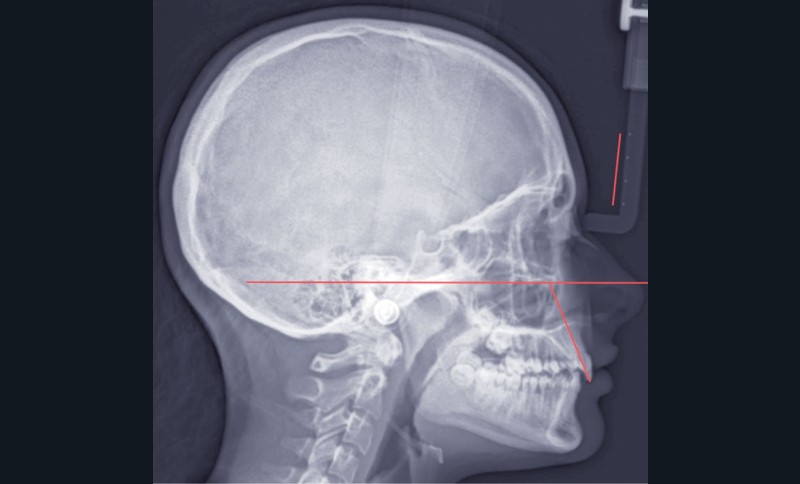

La téléradiographie de début de traitement à 11 ans et demi confirme une évolution en classe I squelettique hypodivergente (fig. 3).